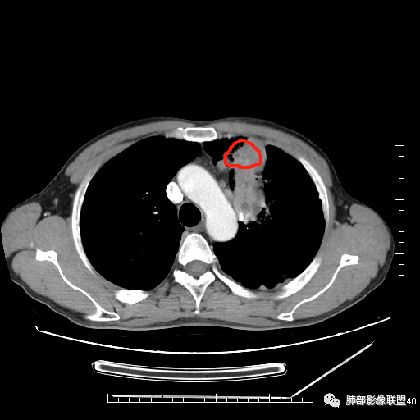

胸CT:左上叶前段团块影,边缘部分清晰,近纵隔侧膨隆明显,分叶,肺侧见平直征,U形凹陷,病灶周围可见磨玻璃影,气肿带,纵隔多发淋巴结肿大,叶间裂多发小结节。增强病灶内密度不均,散在斑片状低密度区,血管造影征。考虑:恶性,鳞?腺?大细胞?鉴别:炎症。似有左侧胸廓内A供血病灶,SFT?

1.左肺上叶尖后段体积变化不大,病灶长轴沿支气管血管束向肺门侧生长,

2.病灶外围大,内带小,外朝内蔓延

6.病灶与纵隔胸膜呈“糊墙”样改变,倾向炎性病灶;

5.  本例的焦点主要集中在结核与周围型肺鳞癌的鉴别诊断上!

病灶与大气道的关系未能满意呈现,但如此大范围病灶紧贴胸膜却未见胸壁纵隔组织结构侵犯破坏是不大符合肺鳞癌的生物学行为的。